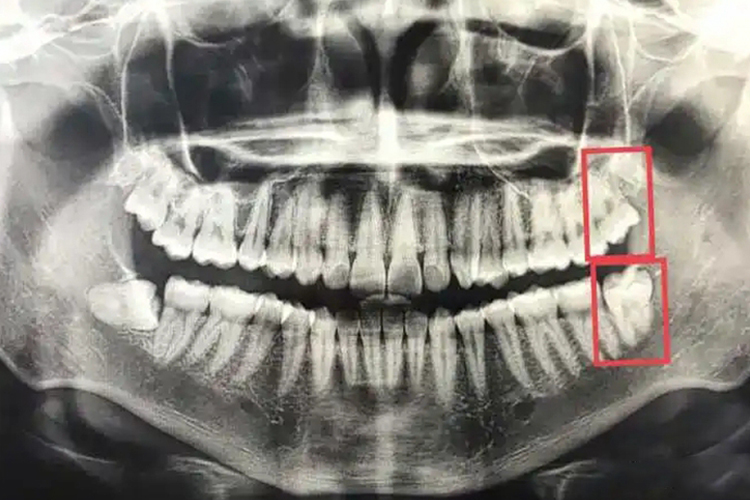

一般情况下,根据阻生智齿,即下颌第三磨牙在颌骨内的深度,可分为高位,中位及低位三类。

高位:对于高位阻生智齿,牙的最高部位平行或高于(牙合)平面。

中位:对于中位阻生智齿,牙的最高部位低于(牙合)平面,但高于第二磨牙的牙颈部。

低位:对于低位阻生智齿,牙的最高部位低于第二磨牙的牙颈部。对于骨埋伏阻生,即牙全部被包埋于骨内现象,也属于低位阻生智齿。

一般情况下,下颌阻生智齿萌出至正常位置,形成良好咬合关系时,应尽量保留牙齿。出现红肿、疼痛等症状时,需积极进行拔出治疗。如高位阻生,多无冠部骨阻力,可去除邻牙阻力后拔除。而低位阻生,冠部骨阻力较大,需去除较多骨质,直至显露牙冠最大直径后方可拔除。